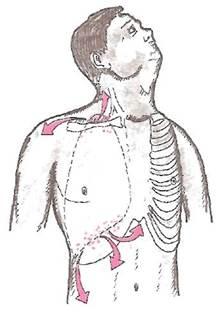

В зависимости от локализации воспаления плевры меняется локализация боли и ее иррадиация (рис. 11).

Рис. 11.

Локализация и иррадиация болей при апикальном и диафрагмальном сухом плеврите

При костальном

фибринозном (сухом) плеврите боли могут локализоваться в различных отделах грудной клетки. Причем боли в левой половине грудной клетки могут отдаленно напоминать затянувшийся приступ стенокардии, что требует проведения дифференциальной диагностики с ИБС. При апикальном

плеврите боли иррадиируют в шею, плечевой сустав.

При диафрагмальном

сухом плеврите боли могут локализоваться или иррадиировать в эпигастралыную область, правое и левое подреберье, подвздошную область, в поясницу, напоминая клинические проявления холецистита, аппендицита, язвенной болезни желудка и 12-перстной кишки, мочекаменной болезни, пиелонефрита и т.п., что может служить причиной серьезных диагностических ошибок.

При вовлечении в патологический процесс диафрагмалъного нерва

боли могут иррадиировать в плечо, шею, а также сопровождаться диспептическими расстройствами — рвотой, неукротимой икотой, продолжающейся па протяжении многих часов и т.п.

Междолевой

фибринозный (сухой) плеврит, осложняющий иногда течение затяжных пневмоний, часто протекает бессимптомно: боли в грудной клетке не выражены или имеют малую интенсивность, возникая лишь на высоте глубокого вдоха.